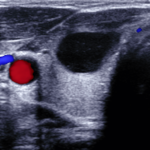

Schilddrüse

Bei der Sonographie der Schilddrüse wird die Größe, die Form und das Gewebe der Schilddrüse sowie eine eventuelle Knotenbildung beurteilt.

Auf dem Bild nebenan sieht man den Blutstrom in der Arteria carotis, der großen Halsschlagader, rot dargestellt. Im oberen rechten Quadranten ist eine rundliche schwarze Struktur erkenntlich, hier liegt eine Zyste der Schilddrüse vor.